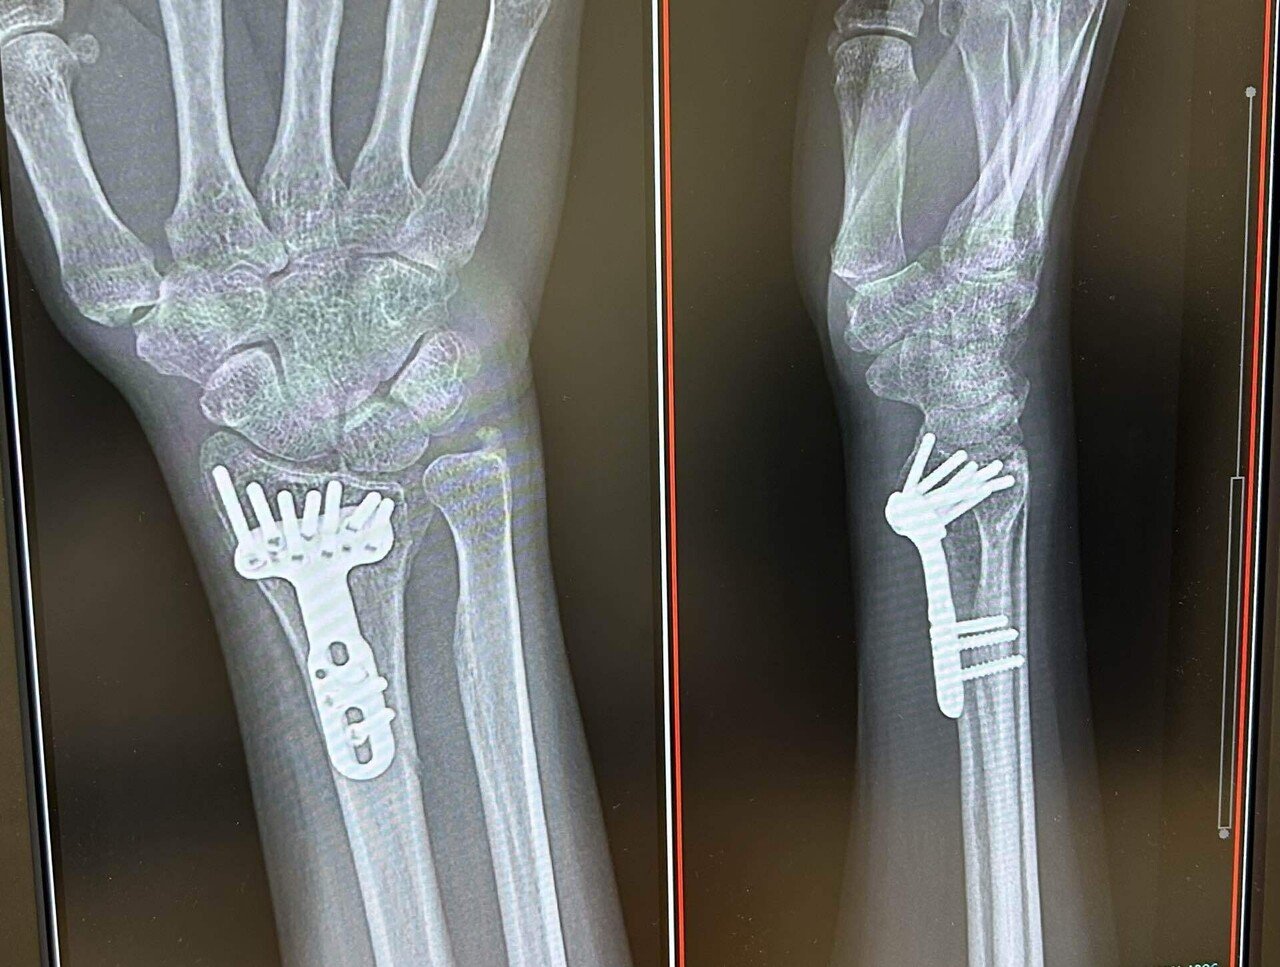

手首 手術手首 プレート手首 51)橈骨遠位端骨折変形治癒手首 橈骨を削る手首 -手首 パープレーを目指す主婦ゴルファー、攻め方やコース内練習場を紹介手首 手首骨折(橈骨遠位端骨折)の治療費(手術費用)はいくら?負担軽減の方法が!?|交通事故の弁護士カタログ手首 橈骨遠位端骨折手首 |手首 ささくら整形と手のクリニック手首 キーンベック病体験記(5)プレートとボルトの除去手首 |手首 人に学びて、自然とともに生きる手首 橈骨遠位端骨折抜釘手術入院手首 記録手首 |手首 keep手首 up